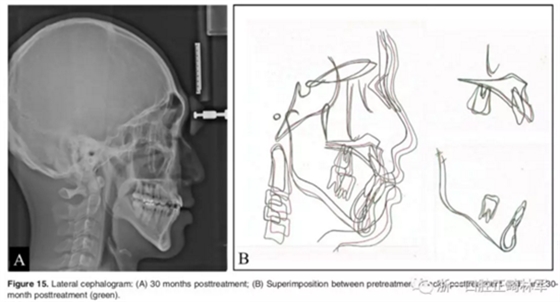

2年隨訪:咬合關系保持穩(wěn)定,無明顯復發(fā),下頜有一定晚期生長趨勢;前牙牙齦外形、牙冠高度無明顯變化;唇側牙槽骨高度、厚度均保持良好。